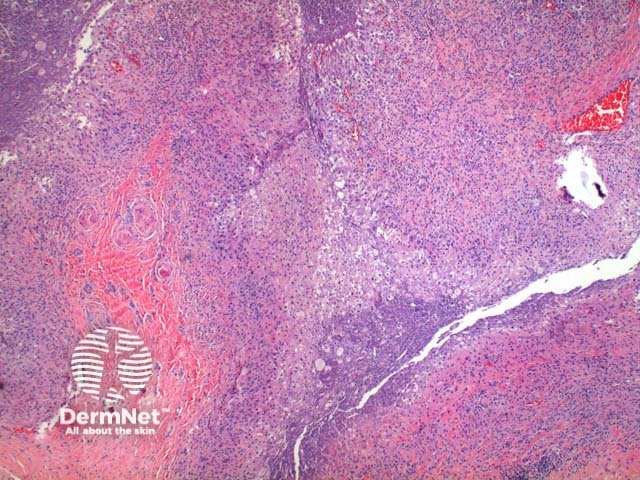

Scanning power view of phaeohyphomycosis shows a deeply extending granulomatous pattern (Figure 1) which may show areas of necrosis (Figure 2). Centrally an abscess or cystic nodule may form. Frequently a foreign body such as a wood splinter can be seen. The epidermis commonly shows pseudoepitheliomatous hyperplasia. The inflammatory infiltrate is comprised of histiocytes with multinucleated giant cells, and numerous neutrophils (Figures 3,4 and 5). At high power branching septate pigmented fungal hyphae can be seen (Figure 6).

Figure 3

Figure 4